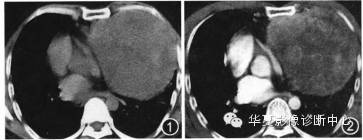

体 检:左侧胸廓饱满,呼吸动度减弱,左下肺叩诊实音,左下肺呼吸音低,未闻及干湿性哕音。胸部CT平扫:示左中纵隔巨大软组织肿块(图1),大小约22.8 cm×17.2 cm×15.8 cm,CT值42—68 HU,密度不均,其内见片状稍低密度影,肿块边界清楚,纵隔受压右移,双肺未见实质性病灶,肺门及纵隔内未见肿大淋巴结。CT增强示肿块明显不均匀强化 (图2),动脉期CT值52—96 HU,静脉期CT值45~86 HU,其内可见斑片样及线条状明显强化影,坏死区未见强化。CT诊断为恶性肿瘤性病变。

图1 CT平扫示左中纵隔巨大软组织肿块,密度不均,边界清楚;图2 CT增强示肿块明显不均匀强化,邻近左前胸壁密度不均,边缘毛糙;